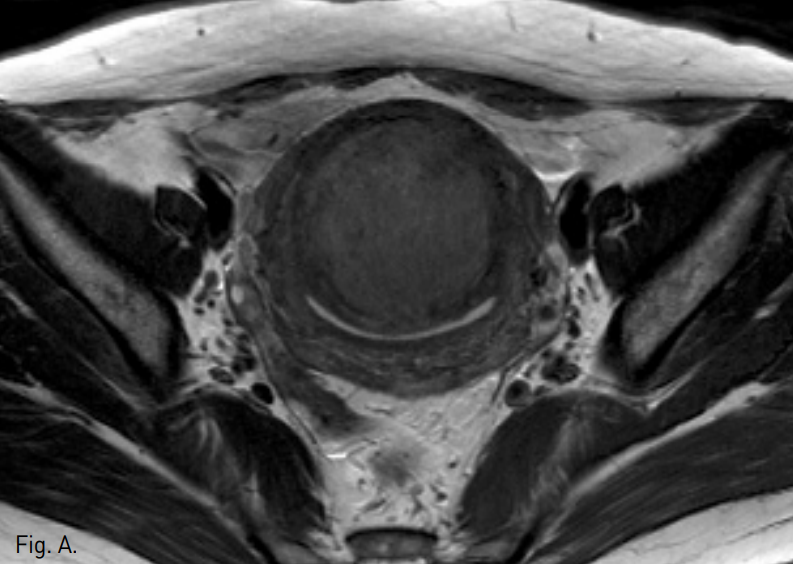

Fig. 2

A-C. T2-weighted transverse (A), coronal (B), and sagi ttal (C) MR images show a huge mass of low signal intensity.